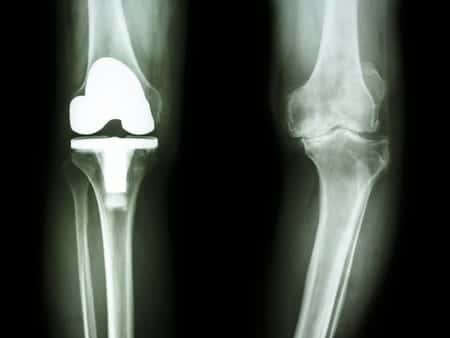

This case involves a sixty-five-year-old male patient who sustained work-related injuries to his right knee. After receiving conservative therapy, the patient underwent arthroscopy and finally a total knee replacement due to painful arthritis. Following the procedure, the patient had complaints of pain and a significantly decreased range of motion compared to before the replacement. X-rays that were taken postoperatively revealed that the patella had not been resurfaced and a revision of the right knee with a downsizing of the prosthesis and recutting of the proximal tibia was recommended. There was some improvement following the revision procedure, however, the patient suffered constant pain in the limb as a result of muscle damage. The substance of the claim was that the prosthetics device utilized by the surgeon during the procedure was improperly sized and that the total knee replacement ultimately failed due to surgical error.